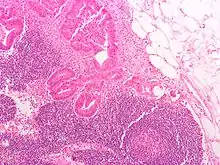

Lymph node tissue showing trabeculae

Thin reticular fibers (reticulin) of reticular connective tissue form a supporting meshwork inside the node.[2] The lymph node capsule is composed of dense irregular connective tissue with some plain collagenous fibers, and a number of membranous processes or trabeculae extend from its internal surface. The trabeculae pass inward, radiating toward the center of the node, for about one-third or one-fourth of the space between the circumference and the center of the node. In some animals they are sufficiently well-marked to divide the peripheral or cortical portion of the node into a number of compartments (nodules), but in humans this arrangement is not obvious. The larger trabeculae springing from the capsule break up into finer bands, and these interlace to form a mesh-work in the central or medullary portion of the node. These trabecular spaces formed by the interlacing trabeculae contain the proper lymph node substance or lymphoid tissue. The node pulp does not, however, completely fill the spaces, but leaves between its outer margin and the enclosing trabeculae a channel or space of uniform width throughout. This is termed the subcapsular sinus (lymph path or lymph sinus). Running across it are a number of finer trabeculae of reticular fibers, mostly covered by ramifying cells.